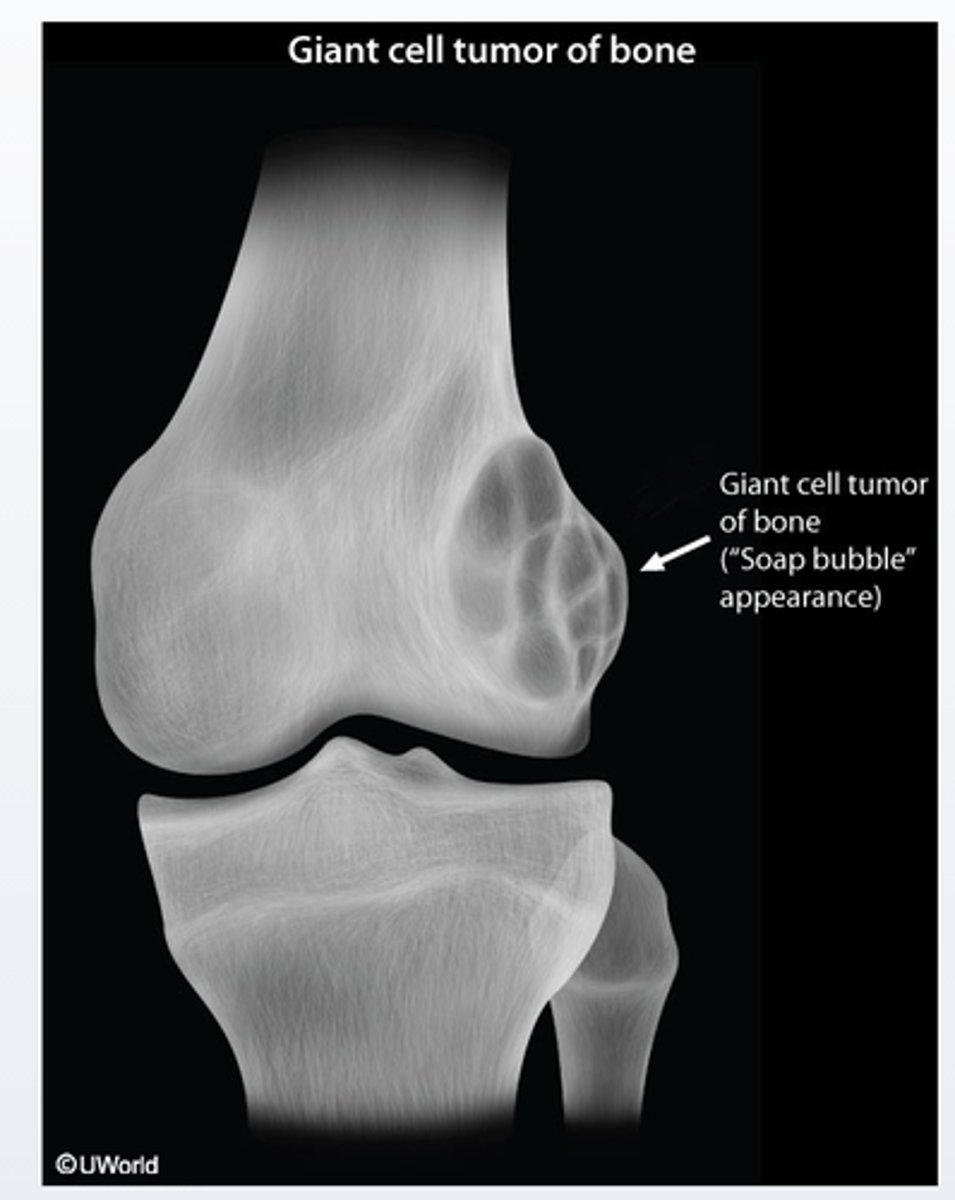

Giant cell tumor

Giant cell tumor of bone is a benign and locally aggressive skeletal neoplasm that usually presents with pain, swelling and decreased range of joint motion at the involve site. It typically presents as osteolytic (with a soap-bubble appearence on radiographs) in the epiphyseal regions of the long bones and most commonly involves the distal femur and proximal tibia around the knee joint